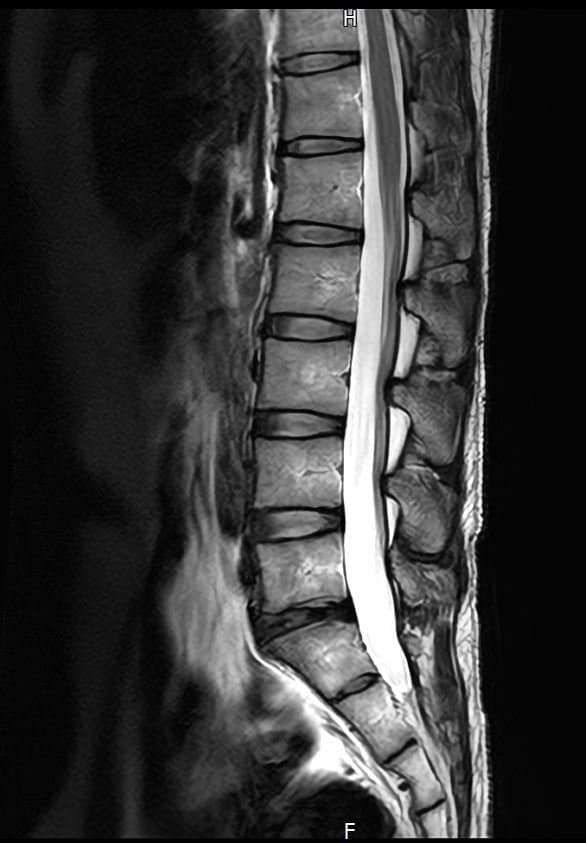

양쪽 엉덩이 염좌 6주째인데 mri 촬영한것좀 봐주세요

엉덩이 양쪽 염좌가 6주됨

방사통 없음 저림 없음 재채기 , 계단타기 전부 정상 , 숙일때 통증 없음

엉덩이 위쪽 바깥쪽 부분이 아픔 압통점 있음

어떤날은 안아프고 어떤날은 약간 아프고 반복

177 / 66kg 약간의 퇴행성이 보인다는데 엉덩이 염좌와는 연관 없을꺼라고 하는데

영상과 증상을 종합해보면 전체적으로 척추배열은 양호하나, 요추4~5번과 요추5번~천추1번 사이의 디스크 수핵이 약간 검게 변한 퇴행성 변화가 관찰됩니다. 다만 신경을 심하게 압박하는 추간판탈출증 소견은 뚜렷하지 않습니다.현재 방사통이나 저림이 없고 특정부위에만 압통이 있다면 의료진의 소견대로 허리디스크보다는 근육 몇 인대문제일 가능성이 높습니다.말씀하신 부위는 염좌로 인해 예민해진 근막이나 인대가 완전히회복되지 않아 컨디션에 따라 통증이 반복될수 있습니다. 6주째 통증이 반복된다면 단순 휴식보다는 물리치료나 도수치료를 통해 굳어있는 근막을 풀어주는 것이 회복에 도움이 됩니다. 빠른쾌유를 빕니다!

MRI 영상상 관절 주변 조직의 부종이나 구체적인 염증 부위를 세밀하게 확인하는 과정이 꼭 필요해 보입니다.